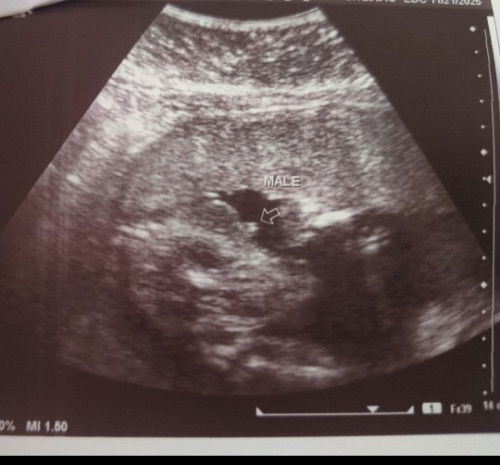

@14 weeks and 1 day nalalaman na talaga ang gender ng baby miiii 😳 Ito talaga bumulagaaaa

same din mihhh sabi nga daw nila mother in law 6 months ata or 7 makikita yung gender ni baby pero nagpa ultra sound na agad kami 4m baby boy din same tayoo!! congrats mihh!!

Amazing talaga miiiii mag gegender pa sana Kami eh peruuu tadaaa, congrats to us!

Ganyan talaga mga boy mi e hahaha daling makita ng gender. Yung sa bunso ko nun e 16wks lang rin ako nung nagpakita siya sa utz, ganyan na ganyan nakabulaka’t nakasilip yung lawit 😂

same mi hahaha. ung nkita agad pototoy non. savi pa ni doc khit d na mgpagender reveal kc kita nmin agad 🤣🤣🤣